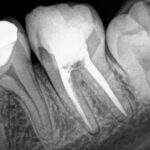

Estas radiografías pertenecen a una paciente que tuvo que realizarse un retratamiento de conducto (es decir que se tuvo que volver a hacer la endodoncia). La paciente presentaba dolor por infección y una pobre obturación con falta de instrumentación de uno de los conductos, (en este molar eran tres y solo se trataron dos y de manera insuficiente). Entonces fue necesario volver a instrumentar (trabajar) los conductos lavando y desinfectando los mismos y por último obturarlos adecuadamente.

La primera radiografía muestra como estaba al venir la paciente y la segunda el trabajo finalizado.

- Aquí el trabajo finalizado con la limpieza y el obturado realizado correctamente.